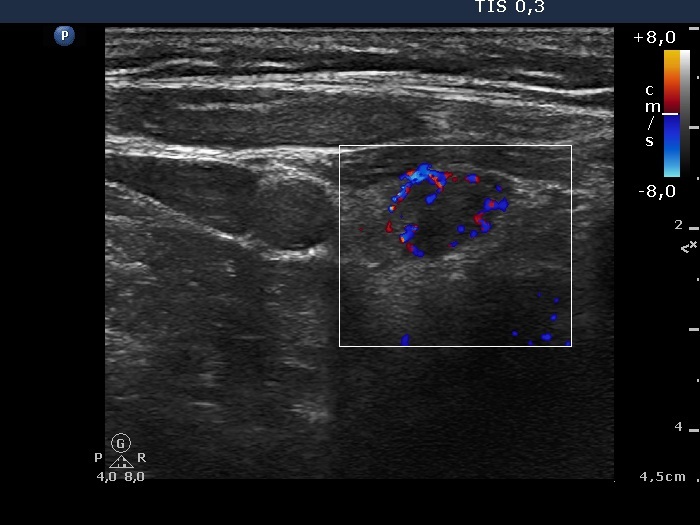

Right lobe, longitudinal scan

Right lobe, transverse scan, color Doppler mode. The nodule has perilesional vascularity.